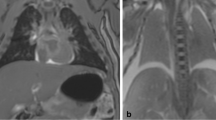

Postmortem imaging now plays a significant role in the paediatric and perinatal less invasive autopsy, with postmortem magnetic resonance imaging (PMMR) demonstrating high overall diagnostic accuracy [1]. However, accuracy is greater for some organs than others, with postmortem changes in the lungs in particular being difficult to distinguish from pathology; pneumonia in particular is both over- and under-diagnosed on paediatric PMMR [2].

Effect of ventilation on abnormal lung areas

Seven patients had areas of lung abnormalities identified on vPMCT. Mean abnormal lung HU did not change significantly with ventilation (pre-vPMCT −45.3 ± 135.2 vs post-PEEP vPMCT −70.5 ± 164.5; p = 0.70; Fig. 4; Table 1). In two cases, lung consolidation or collapse was identified on vPMCT but not confirmed at autopsy; in one case, this may have been due to a sampling error as the lingula was not sampled at autopsy (Fig. 5; case 9). In one other case, patchy consolidation was identified in a child who also developed a pneumothorax following vPMCT, which may have led to under-aeration of the lungs and a false positive diagnosis. All five cases in which the vPMCT appearances were normal were confirmed as normal at autopsy. Preliminary sensitivity and specificity of vPMCT were 100 % (95 % CI 51.5, 100) and 62.5 % respectively (95 % CI 30.6, 86.2; Table 2). The negative predictive value was 100 % (95 % CI 56.5, 100).

Following ventilation and lung expansion, PMCT could be used to distinguish between normal and abnormal lungs in children, since inflation of the normal lung helped to identify abnormal areas of uninflated lung. The HU of lung areas which did not change significantly following ventilation were associated with true lung pathology, including pneumonia and chronic lung disease of prematurity, although this finding was also associated with false positive diagnoses. Interestingly, one of these false positives was made in a case which underwent a pneumothorax as a complication of vPMCT, implying that the lungs were incompletely inflated (Table 1), which may lead to over-interpretation of collapsed or underinflated lungs.

These studies are largely in agreement with other PM imaging modalities: PMMR has been evaluated to detect lung pathology in the paediatric autopsy setting and has been shown to be relatively insensitive to several different types of pathology, with pneumonia particularly difficult to identify on conventional PMMR imaging [2]. Our results suggest that vPMCT may be of use in differentiating normal from abnormal lung areas, although ventilated PMMR may give similar results, provided MR-compatible airways and ventilation techniques are used, although this remains to be evaluated.